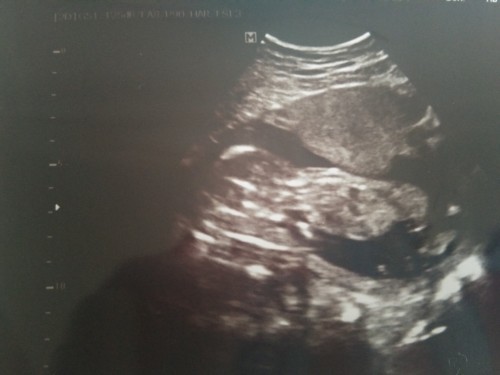

4เดือน น้องยังอาย ไม่ให้เห็นเพศเลยยย หมอบอกนอนคว้ำอยู่